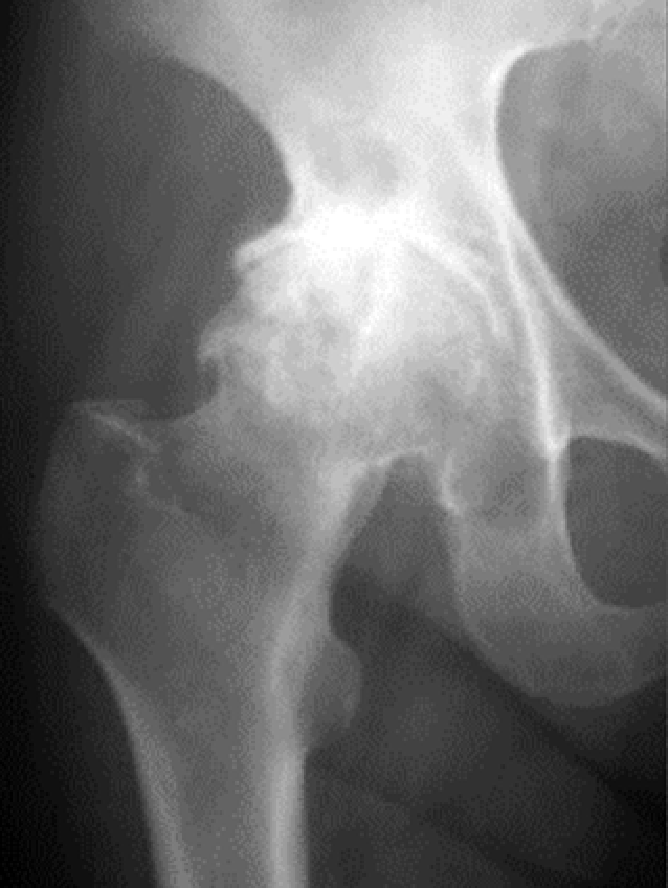

主な股関節症には、変形性股関節症(図4)、大腿骨頭壊死症(図5)、関節リウマチ(図6)などがあります。

図4. 変形性股関節症

図5. 大腿骨頭壊死症

(赤矢印が骨頭壊死部分)

図6. リウマチ性股関節症